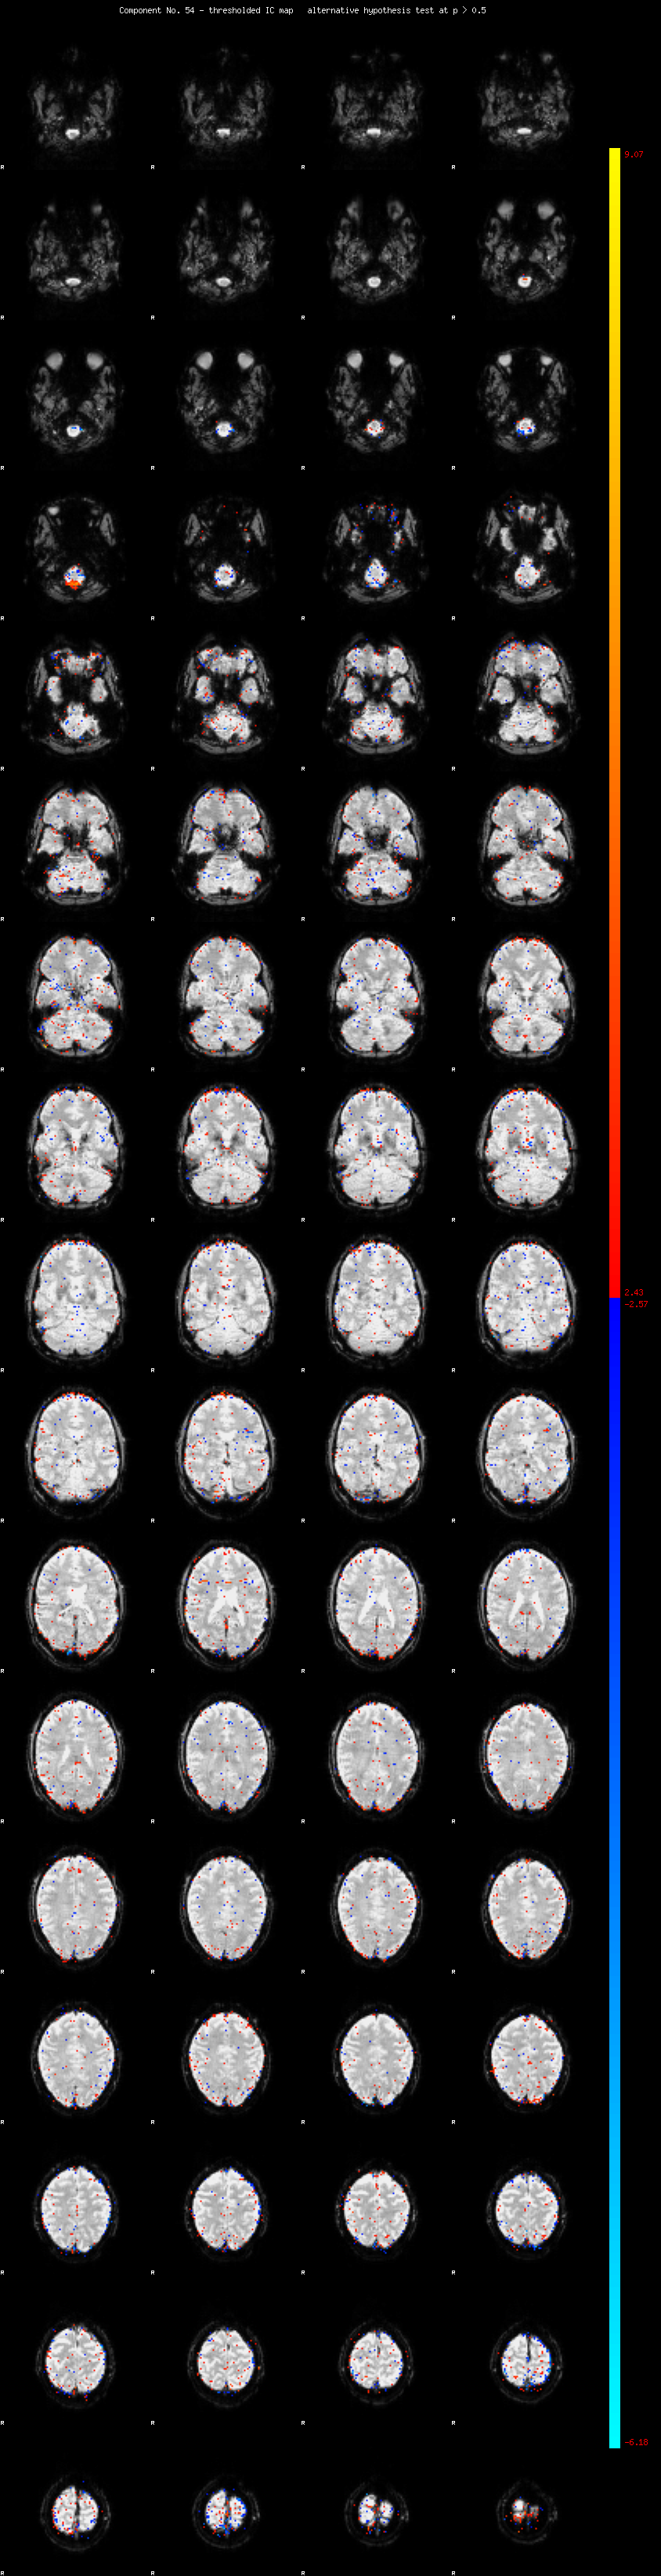

MELODIC Component 54

0.92 % of explained variance;     0.61 % of total variance